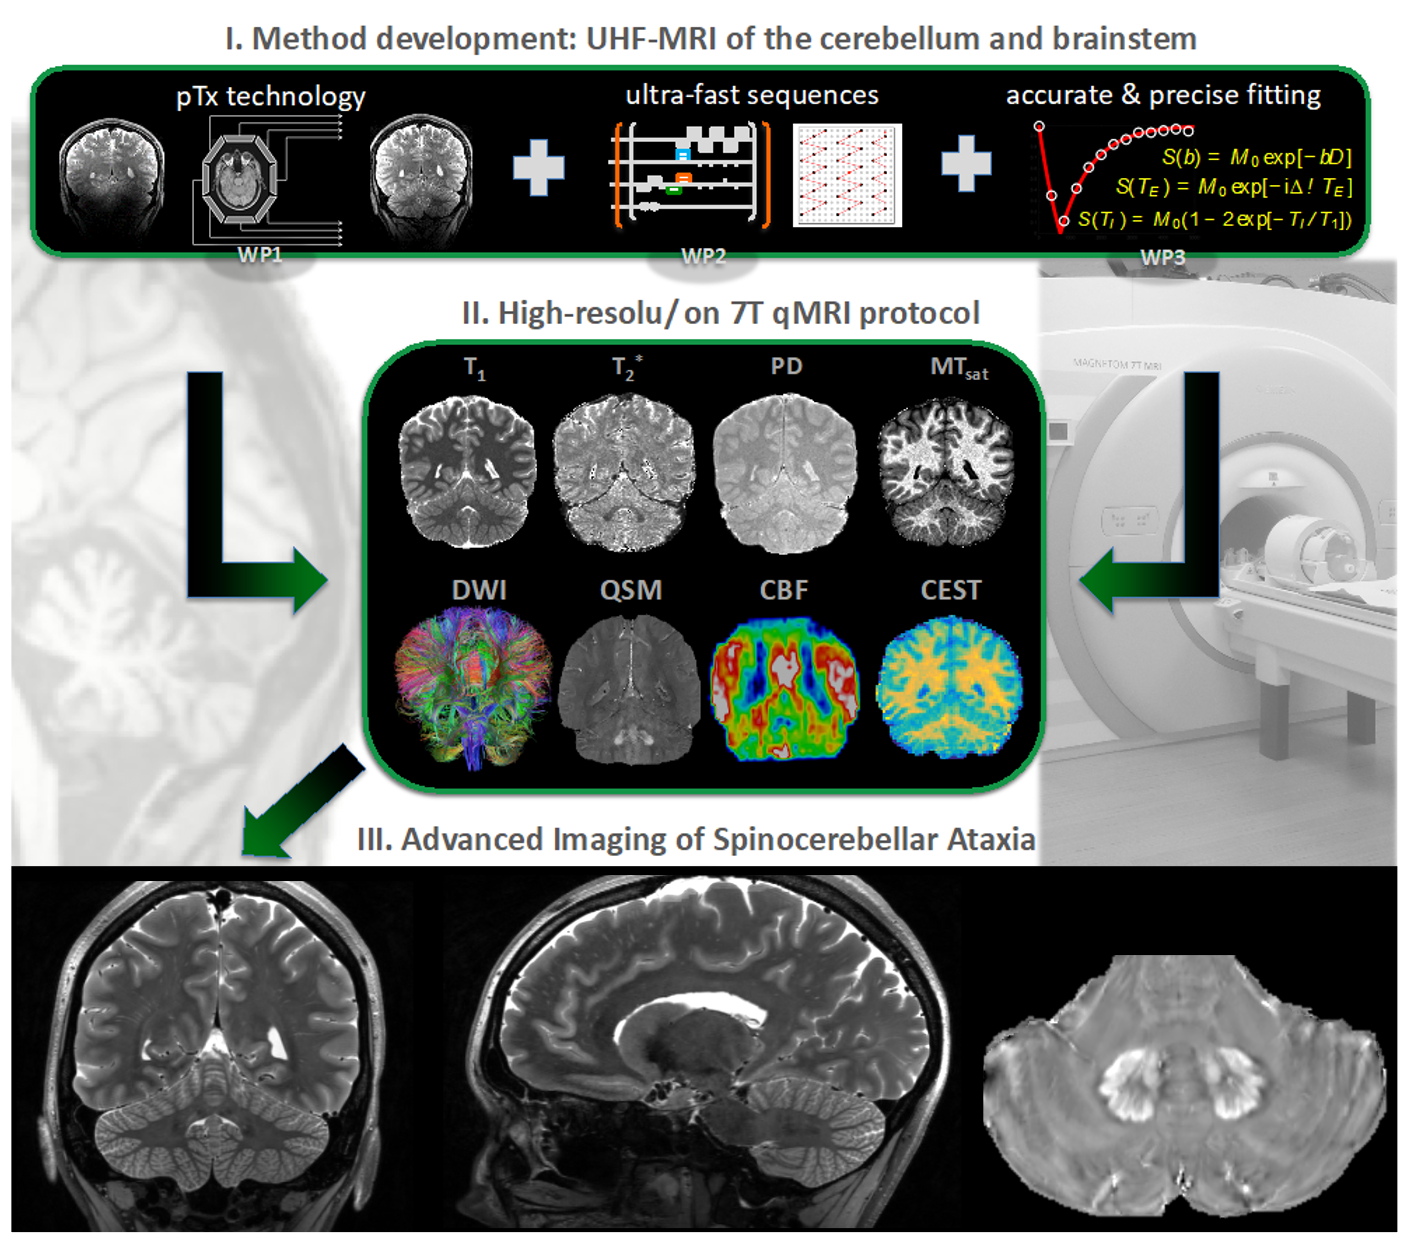

Ultra Highfield MRI

Ultra-high magnetic fields (UHF) offer significantly higher resolutions and advanced MR applications, such as iron-sensitive sequences and metabolic imaging. Thus, UHF-MR has an enormous potential to detect and monitor structural and chemical alterations at a. level of detail that cannot be achieved with a conventional fieldstrength of 3T. However, these clear advantages are opposed by technical shortcommings of field inhomogeneities, which fundamentally degrade image quality, particularly at the excentric infratentorial regions of the field of view. In collaboration with the MR Physics group at the DZNE, lead by Tony Stöcker, we have successfully implemented a comprehensive protocol including structural and metabolic sequences (T1w, T2w, FLAIR, MPM, QSM, CEST) using parallel transmission technologies (pTx) that allows imaging of the entire brain including brainstem and cerebellum in consistently high resolution without artifacts at a fieldstrength of 7T. The acquisition in patients suffering from movement disorders is currently ongoing. We hypothesize, that the increased sensitivity of UHF-MRI has the potential to substantially improve the understanding of structural and metabolic brain alterations in neurodegenerative diseases.

Automated Segmentations & AI-driven MRI Analysis

Leveraging cutting-edge artificial intelligence (AI) methods, we analyze MRI images to identify disease specific alterations. We have successfully implemented CerebNet, a fast and reliable deep-learning pipeline for detailed cerebellum sub-segmentation with high anatomical accuracy (Code on Github). Further development of CerebNet is underway, with extensions for sub-segmentation of high-resolution MRI and inclusion of the brainstem and cerebellar peduncles. Moreover, we are implementing segment anything pipelines as well as unsupervised surface analyses. Our objective is to enhance our understanding of disease related structural changes. By discerning subtle changes in the brain, we aim to contribute valuable insights that may not only deepen our comprehension of the disease but also foster the development of novel treatments by informing the design of clinical trials.

Imaging Biomarkers in Ataxias

One of our main research aims is the identification of robust and reliable MR imaging biomarkers, particularly in sporadic and hereditary ataxias. Imaging biomarkers may serve as diagnostic markers, supporting early and accurate diagnosis e.g. in sporadic diseases, or as marker for progression as well as stratification, e.g. in mutation carriers close to their imminent ataxia onset. For this purpose, we combine quantitative as well as qualitative information derived from advanced MR imaging. By gaining knowledge in this field, we aim to contribute to the development of targeted interventions and personalized treatment strategies.